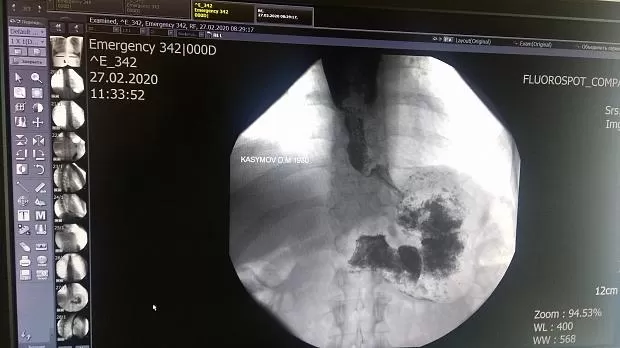

Проведена пневмодилятация кардии баллоном 20х80 мм до 2,5 атм  с  экпозицией до 5мин. При контрольном осмотре ПЖП проходит свободно и ренгенологически расширение до 1,2 см. Планируется 2-й этап пневмодилятации.